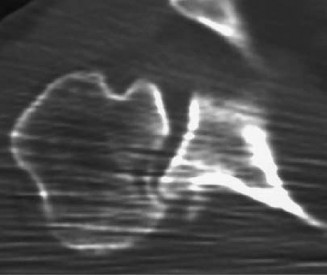

Identify the muscles that compose the force couples in the transverse and coronal planes? CASE 3 A 35-year-old male has had left shoulder pain for 4 months, ever since a low-speed motor vehicle accident (MVA). Physical examination demonstrates preserved range of motion but pain and some weakness with Jobe’s testing. His imaging is shown in Figure 2–8.

Figure 2–8_Reproduced with permission from Stadnick ME. _Partial Rotator Cuff Tears. MRI Web Clinic. 2007 (Apr).

What is the most likely diagnosis?

The correct answer is (A). These are best diagnosed on an MRI as seen in the imaging provided; addition of intra-articular contrast can further improve this study. Answer B, full-thickness rotator cuff tear, is incorrect as the bursal side of the tendon can be seen to be in continuity. Answer C, a SLAP lesion, will be visualized as a labral tear on a coronal MRI and will be found at the biceps root. Answer D, an ALPSA lesion, will be most clearly seen on an axial MRI. It is a variant of a Bankart lesion where the labrum is displaced medially and inferiorly rolling down the glenoid neck underneath the periosteum.

MRI remains the most popular imaging modality for diagnosing rotator cuff tears. Normal rotator cuff tendon appears dark on both T1 and T2 sequences. Tears may be noted as being full-thickness, articular-sided, bursal-sided, or intrasubstance. They are visualized as a disruption in the regular contour of the tendon and increased signal intensity on T2 sequences. Occasionally, an MR arthrogram may provide additional information regarding a cuff tear, although this is not routinely ordered.